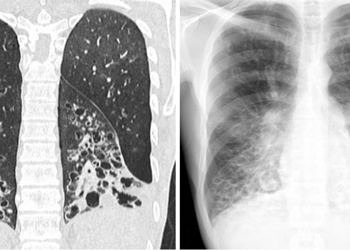

DevamıBronşiolit, inflamatuar bir reaksiyondur. Bu reaksiyon çapı 2mm'nin altında olan küçük iletken hava yollarındaki bronşiol epitelinin hasarlanması sonucu ortaya çıkar. İnflamatuar proçes iyileşirken hava yollarının duvarında, lümeninde...